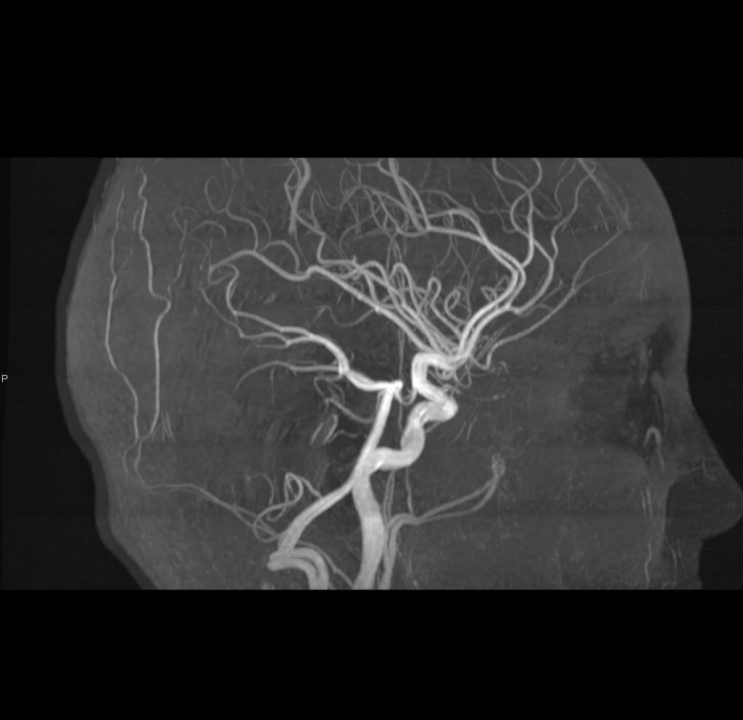

Tijekom Tjedna mozga Poliklinika Affidea Vita daje 20 posto popusta na magnetsku rezonancu!

Povodom obilježavanja Tjedna mozga od 11.

MR angiografija